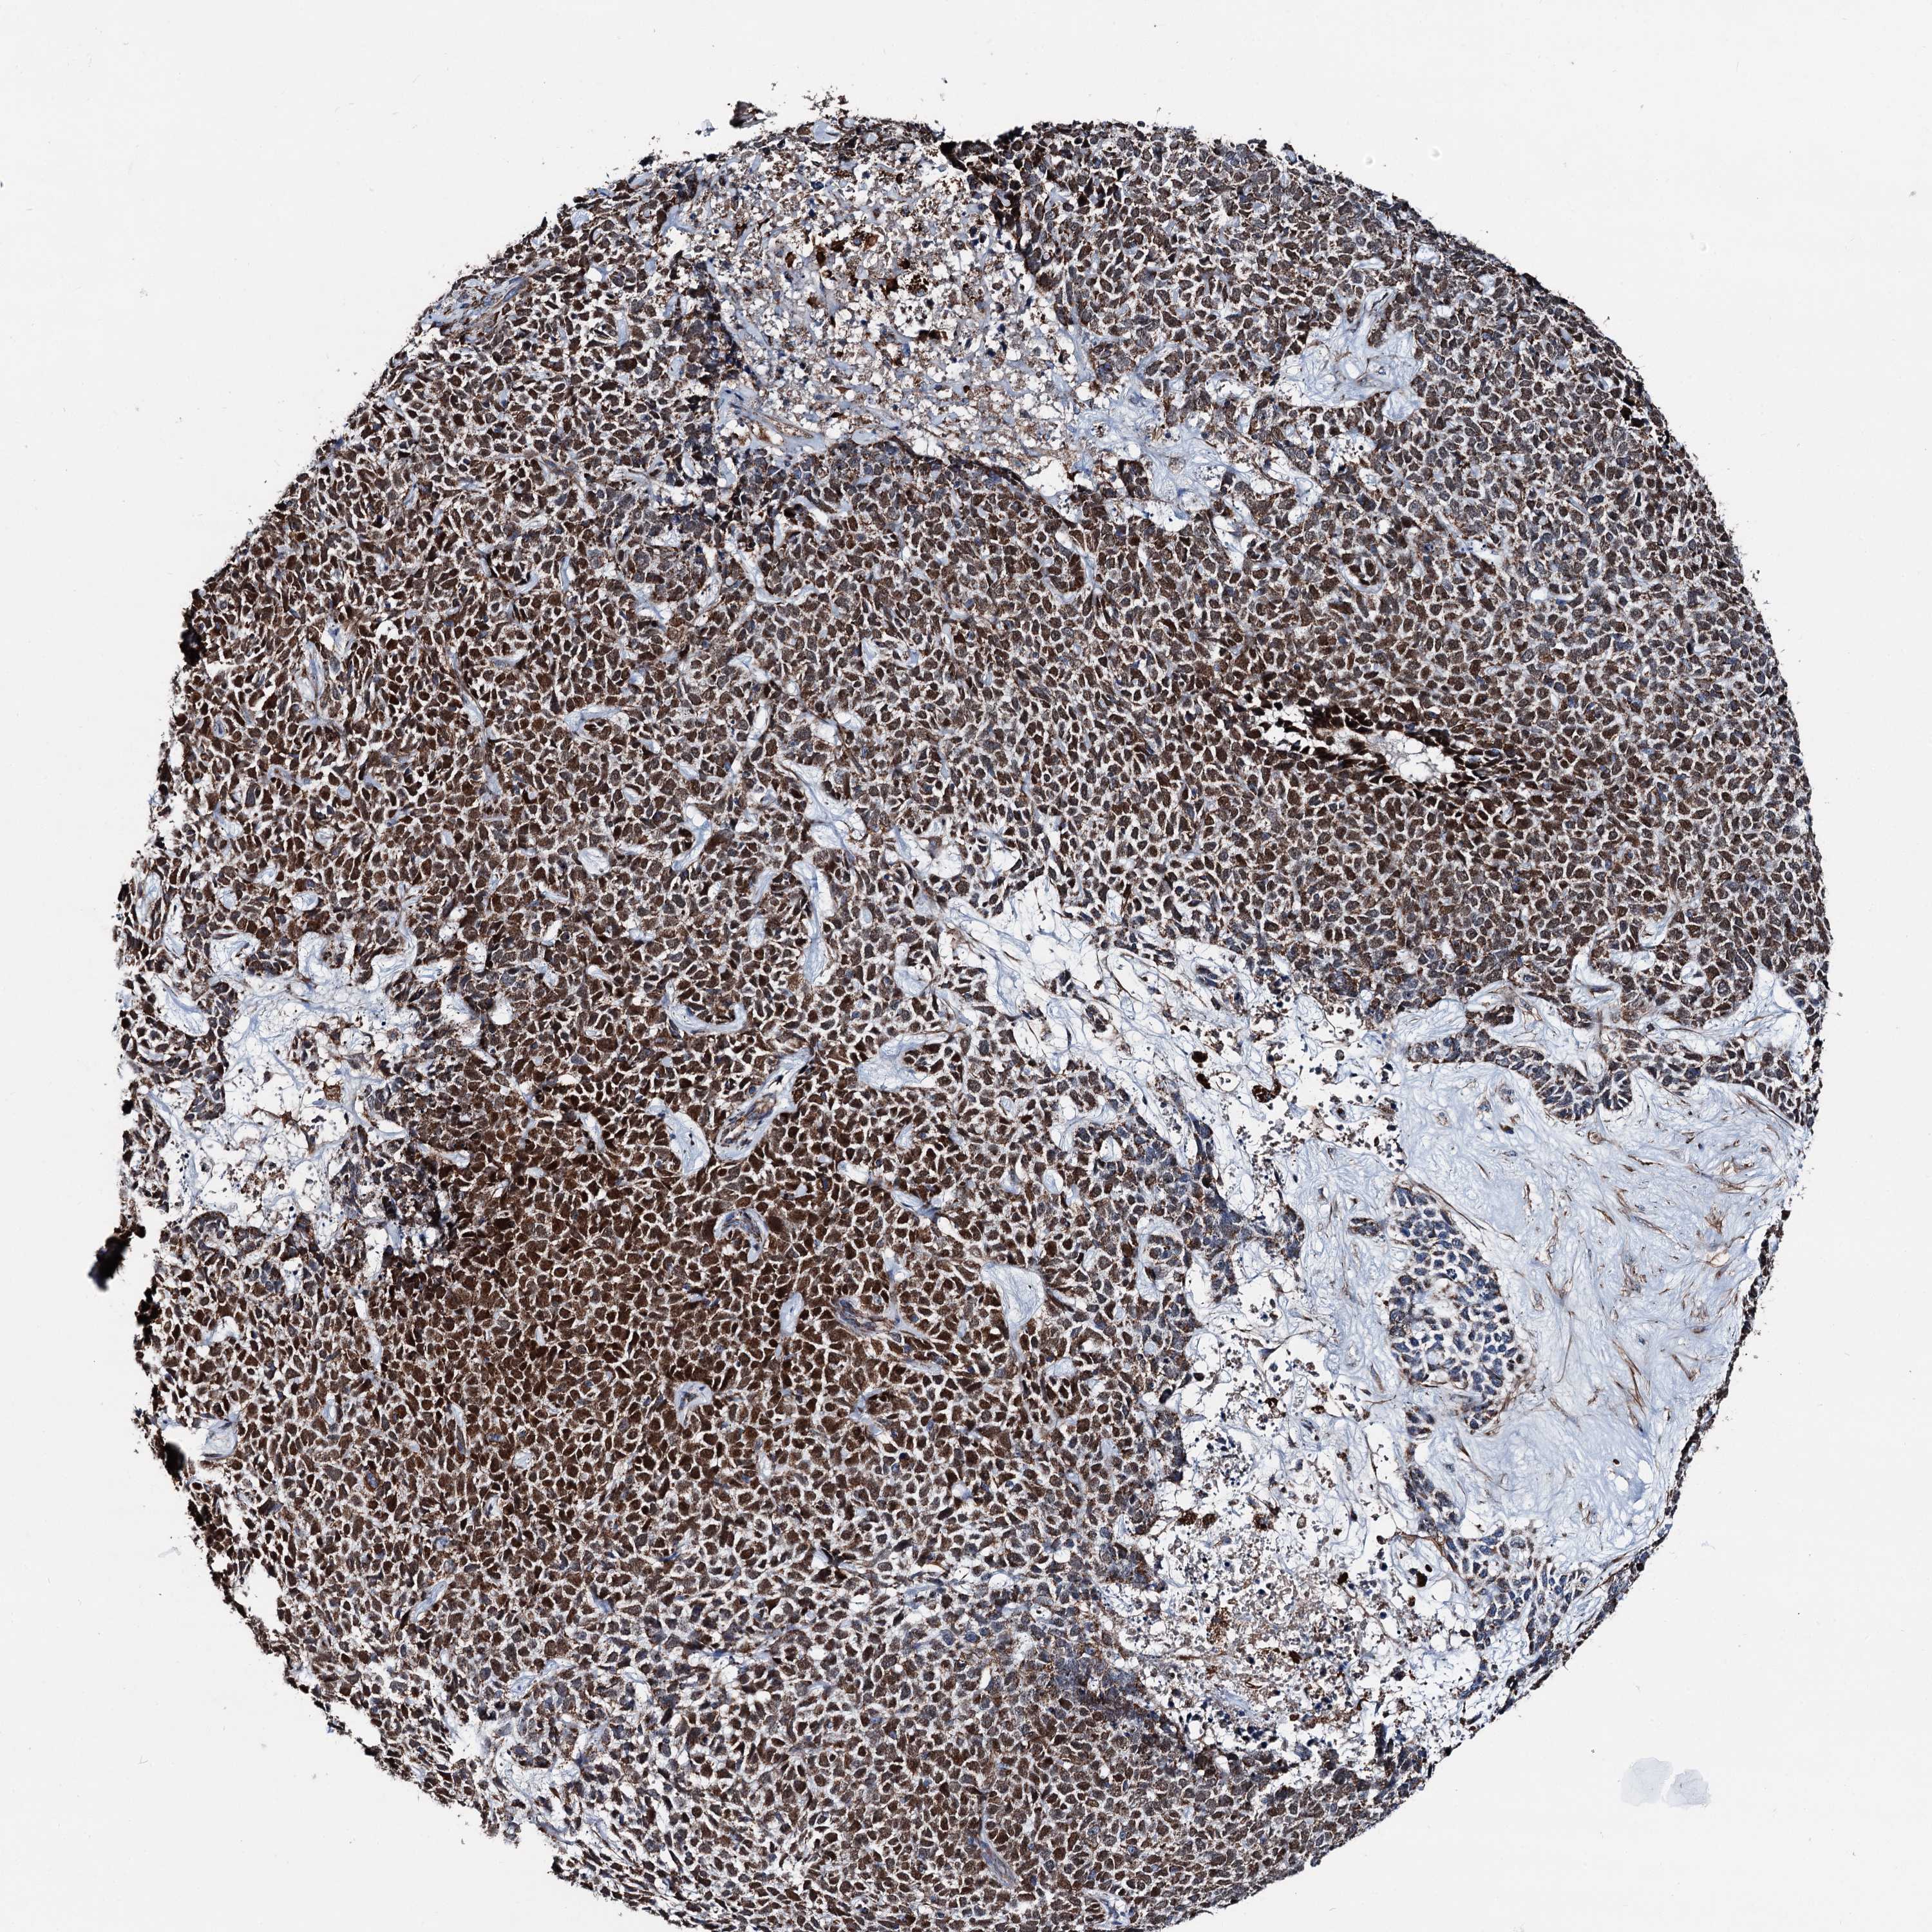

SKIN CANCER - Protein expressioni

A mouse-over function shows sample information and annotation data. Click on an image to view it in a full screen mode. Samples can be filtered based on level of antibody staining by selecting one or several of the following categories: high, medium, low and not detected. The assay and annotation is described here.

Antibody staining in the annotated cell types in the current human tissue is reported as not detected, low, medium, or high, based on conventional immunohistochemistry profiling in selected tissues. This score is based on the combination of the staining intensity and fraction of stained cells.

Each image is clickable and will lead to virtual microscopy that enables deeper exploration of all samples and also displays staining intensity scores, fraction scores and subcellular localization as well as patient and tissue information for each sample.

Antibody HPA038540

Staining

High

Basal cell carcinoma